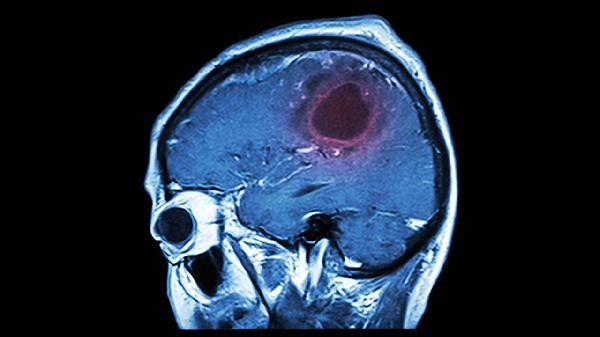

脑溢血的开颅手术时间延长确实可能增加手术风险。手术时间过长可能导致感染概率上升、脑组织暴露时间增加以及术后恢复难度加大。但手术时长并非唯一风险因素,患者个体差异、出血部位及术前状态等均会影响手术安全性。

开颅手术过程中,随着时间推移,麻醉药物代谢可能对生理功能产生累积影响,增加心肺负担。手术创面暴露于外界环境的时间延长,会提升细菌定植机会,尤其对于免疫功能低下或合并糖尿病的患者更为显著。持续牵拉脑组织可能造成局部缺血,影响神经功能恢复,特别是处理深部出血灶时,精细操作需求常导致手术时间自然延长。

某些复杂病例必须延长手术时间以确保彻底清除血肿,如脑干周围出血或血管畸形破裂。高龄患者或术前已发生脑疝者,其对长时间手术的耐受性明显下降,此时需权衡彻底止血与手术时长的关系。术中出现难以控制的渗血或发现意外血管变异时,为保障手术质量可能不得不延长操作时间。